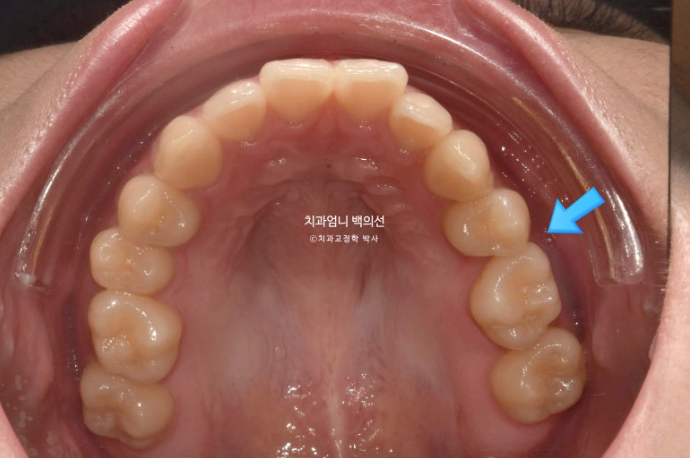

파란 화살표가 원래 작은어금니가 하나 더 있어야할 자리, 즉 선천적으로 결손된 작은어금니 자리입니다.

다행인건 가용한 사랑니 공간이 충분한 점입니다.

입매 돌출감이 미미하여 비발치 치료 권유드렸습니다.

즉 작은어금니 발치 없이 사랑니 공간을 이용하여 교합을 맞추고 중심선을 맞추기로 했습니다.